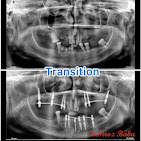

We provide comprehensive dental care using modern techniques and advanced technologies. Whether you'... re looking for braces, cosmetic smile corrections, or full-mouth implants, our team delivers precise, comfortable, and long-lasting treatments that restore confidence and oral health. Your smile is in safe hands with our expert dental care professionals. Read more